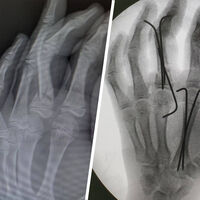

Юноша попал Московский областной центр охраны материнства и детства (МОЦОМД) с тяжелой травмой левой кисти после неудачного прыжка с тарзанки. У мальчика диагностировали открытый оскольчатый перелом среднего и указательного пальцев, а также большую рваную рану.

Врачи оперативно провели хирургическую обработку, восстановили костные фрагменты и зафиксировали их с помощью металлоконструкций, что помогло избежать серьезных осложнений.